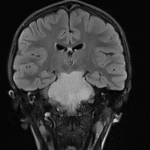

- Masslike area of T2/FLAIR signal hyperintensity involving the pons, midbrain including the cerebral peduncles, left eccentric medulla, and left greater than right middle cerebellar peduncles

- Corresponding faint restricted diffusion in the ventral aspect of the pons

- The mass bulges into the prepontine cistern and at least partially encases the basilar artery

- Associated mass effect on the fourth ventricle without overt hydrocephalus

Diffuse midline glioma